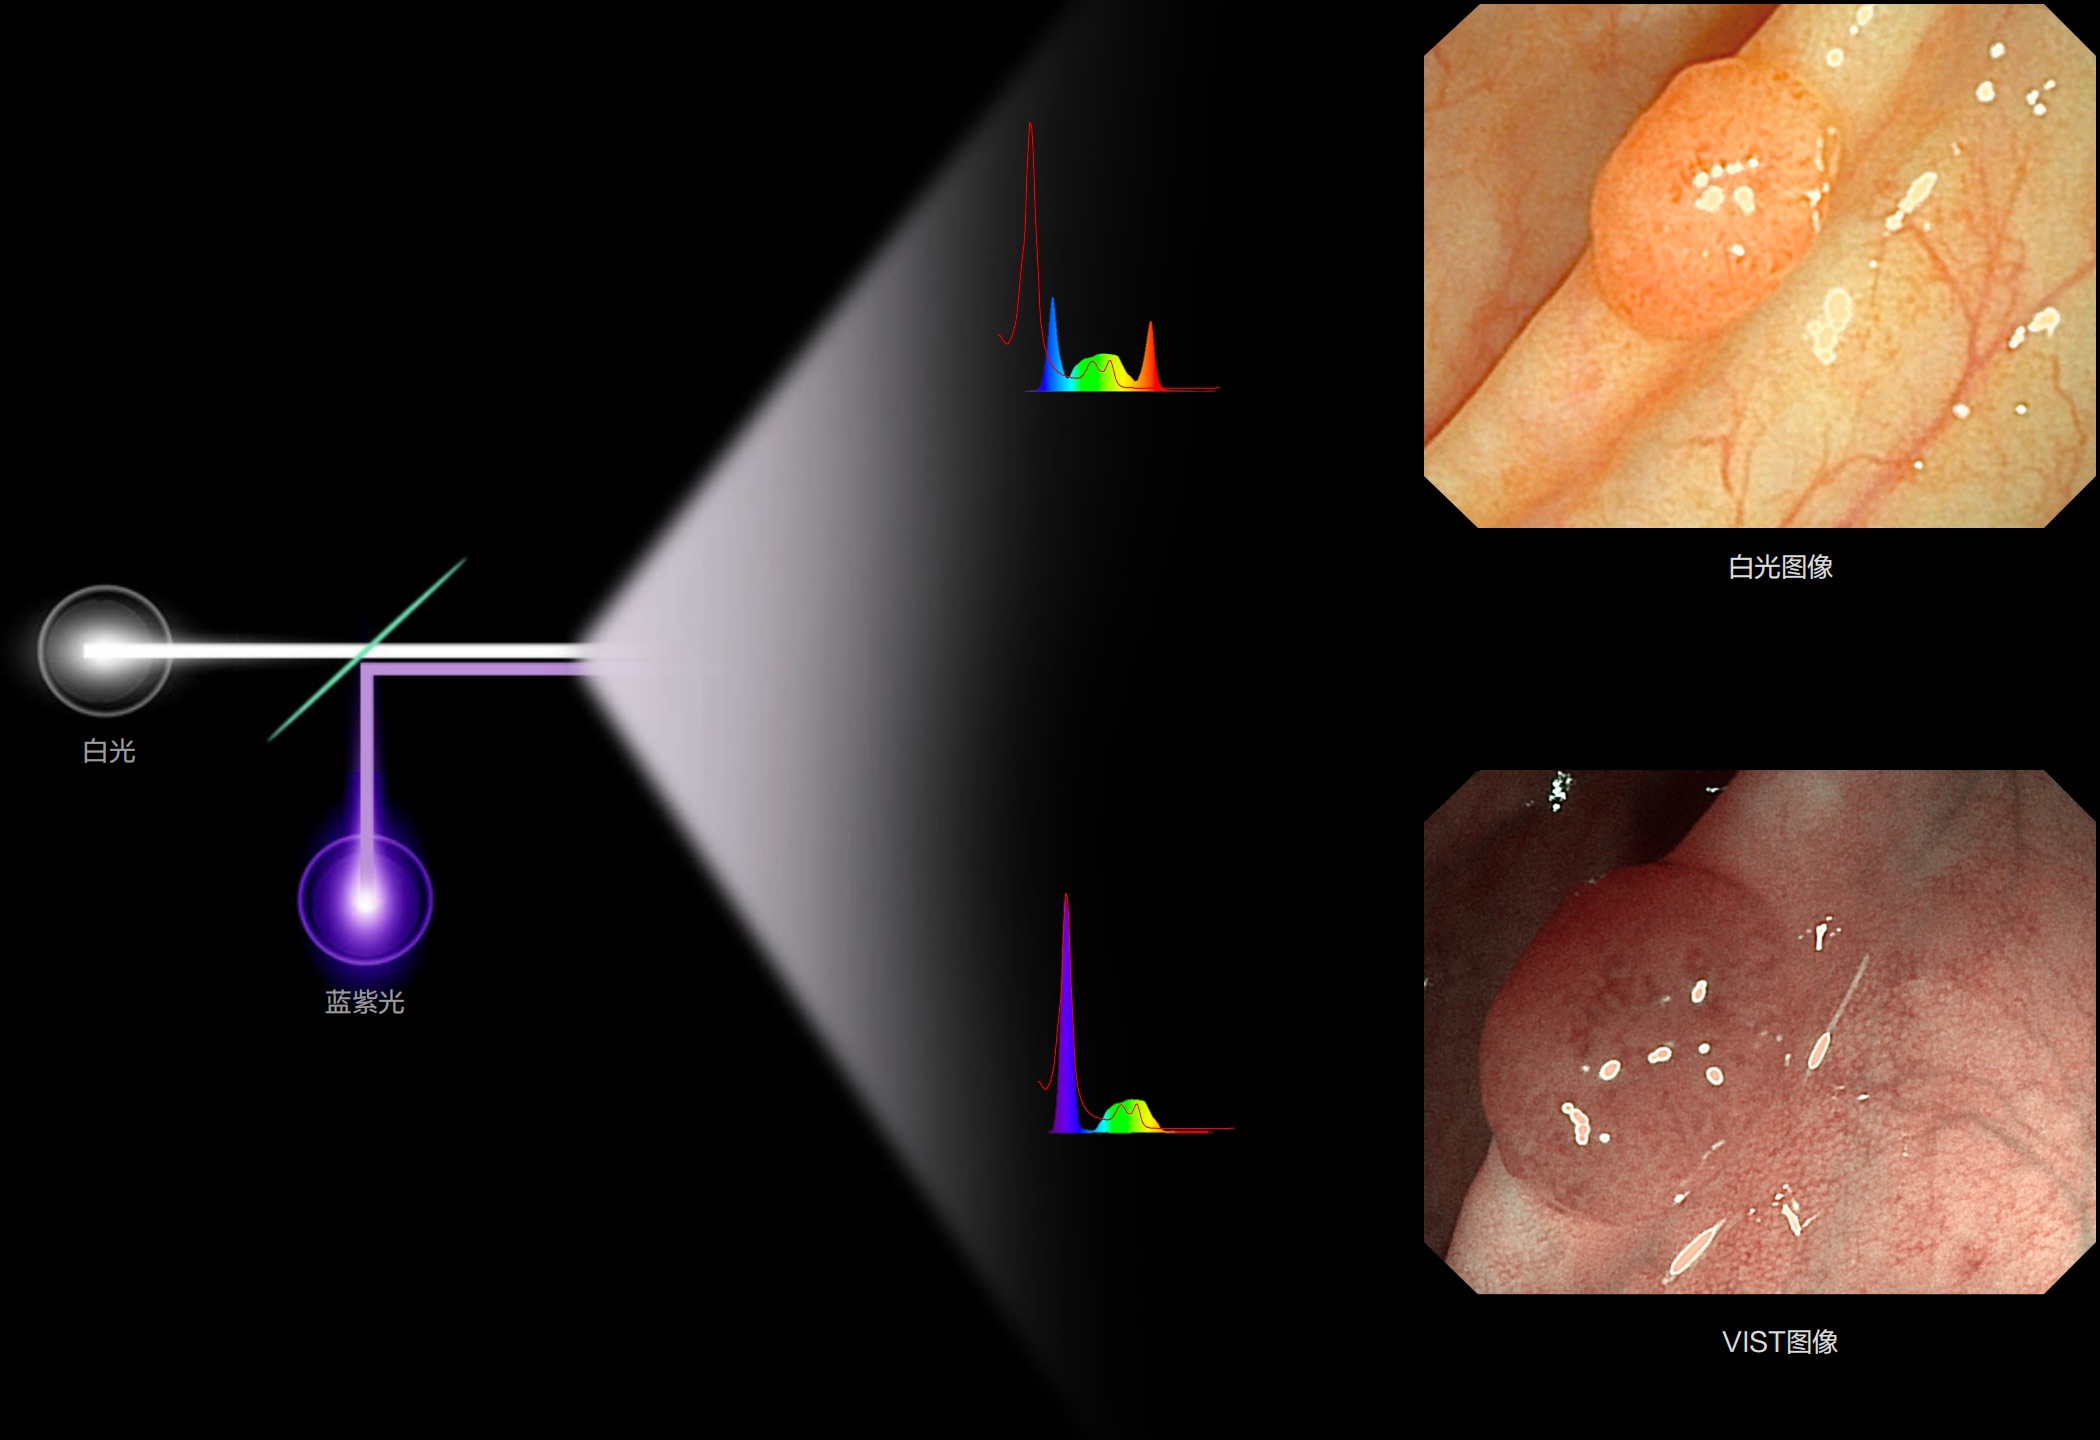

(Versatile Intelligent Staining Technology)

利用了血红蛋白在不同波长吸收下系数不同的原理,设计的一种光学域滤波和数字域滤波结合的染色技术,既保证了图像亮度,又可增强黏膜血管的对比度,充分凸显早期病变的细微结构变化,为临床疾病的观察诊断提供更丰富的参考信息。

白光图像

SFI图像